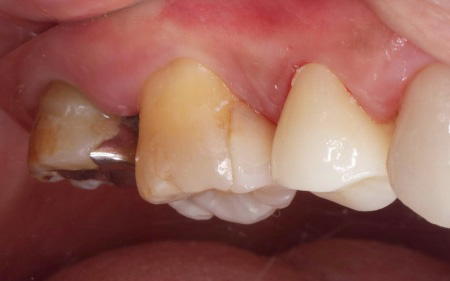

次に、歯を保護するための被せ物「ジルコニアクラウン」を装着します。

ジルコニアは強度が高く、自然な白さが特徴です。

最後に、痛みや違和感がないか、問題なく噛むことができるかを確認し、治療を終了しています。